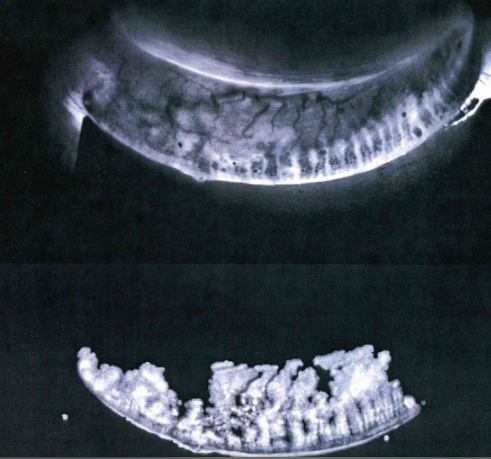

Case 2

This is a 57 year old patient who came in with an acute stye that was present for about 7-10 days before incision and drainage.

This is his Right Eye.

This is his left eye below.

Again many glands missing. He has a long history of mild rosacea blepharitis and it is likely just that, given no symptoms of dry mouth or arthritis.